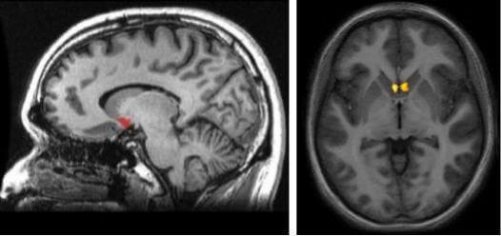

Each brain hemisphere has a nucleus accumbens. They shape your complex reward system. Thanks to this area of the brain, you feel pleasure, lay down new pieces of knowledge, and find the motivation you need for your daily life.

Each of the brain hemispheres has its own nucleus accumbens. That way, the reward system managed through dopamine reaches each part of the brain. This structure is also part of the basal ganglia. As such, one of the most significant characteristics of the nucleus accumbens is the extent to which it’s connected to other parts of the brain.